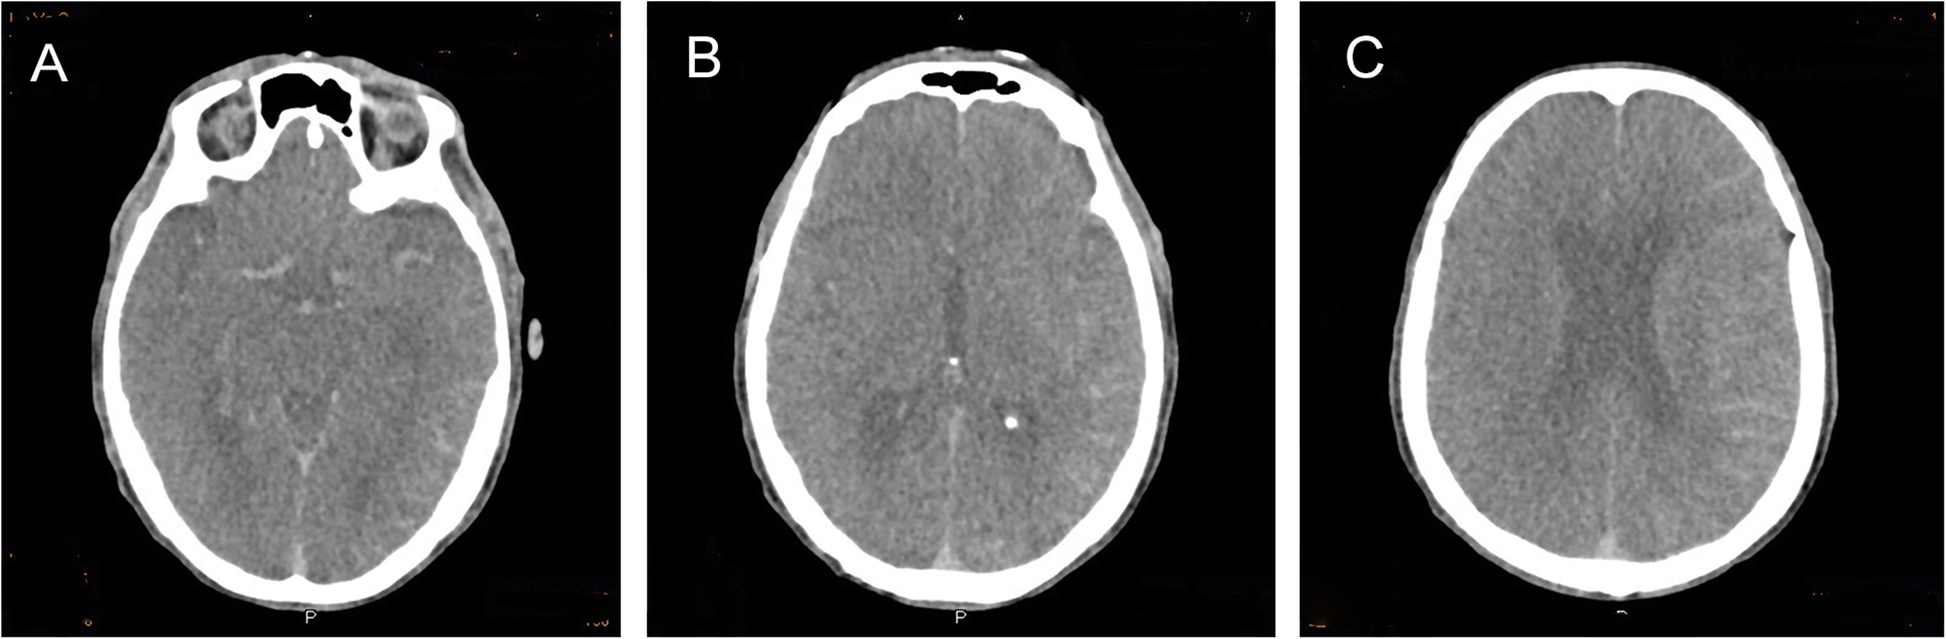

Fig. 2From: Application of spectral CT in the diagnosis of contrast encephalopathy following carotid artery stenting: a case reportCT scan of the patient’s head at onset; a-c: Swelling of the left cerebral hemisphere and left linear high-density areaBack to article page